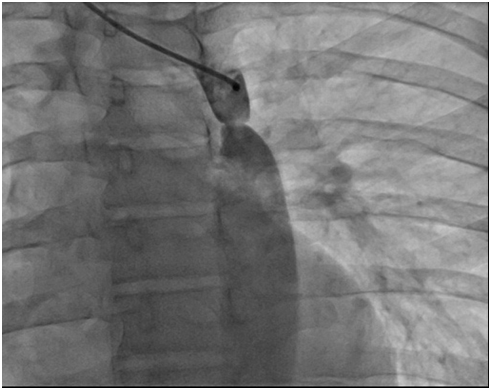

Coarctation of the aorta (CoA) is a congenital heart disease, it occur rarely during the life after trauma ,in cases of advance form of atherosclerosis of aorta and in Takayasu aortitis. CoA is defined as a constricted segment of thoracic aorta at the insertion of ductus arteriosus or a long segment of the hypoplasia of aorta..Sometimes coarctation may be in low segments of thoracic aorta and rarely on the abdominal aorta. It may occur with other form of valvular disease like bicuspid aortic valve, different levels of aortic stenosis or mitral valvular stenosis. In the past CoA has been described as preductal, ductal and postductal type (more common in adults) depending on whether the coarctation segment is proximal or distal to the ductus arteriosus, but now all are juxtaductal (the hemodynamic changes between 3 types are not significant) [1,2] (Figure 1).

Figure 1: Types of coarctation of aorta A-preductal B-ductal C-postductal.